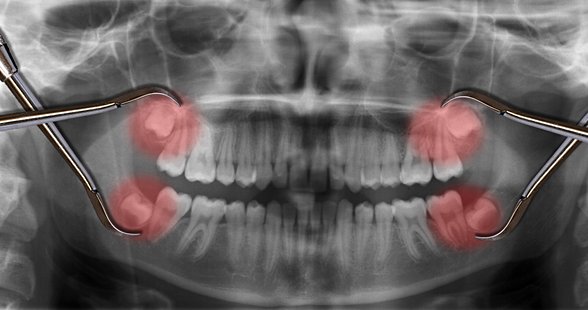

Uzun yıllar insanlar bu dişlerin en başından neden var olduğunu anlayamamış ve bir çeşit "lanet" olarak görmüşlerdir; zira 20 yaş dişlerinin çıkmaya başlamasından çekilene kadar verdiği acıyı, bu dişleri sorunlu olarak çıkan kişiler gayet iyi bilirler. Ancak evrimsel biyolojinin gelişimiyle birlikte öncelikle insan evrimine ışık tutulmuş, daha sonra da bu tip körelmiş organların varlığı açıklanmıştır. 20 yaş dişleri de, insanda görülen 40'tan fazla körelmiş organ ve yapıdan sadece birisidir. Aşağıda, bu körelmiş yapıların ne şekilde hatalı oluşabileceklerine örnekler görülmektedir: